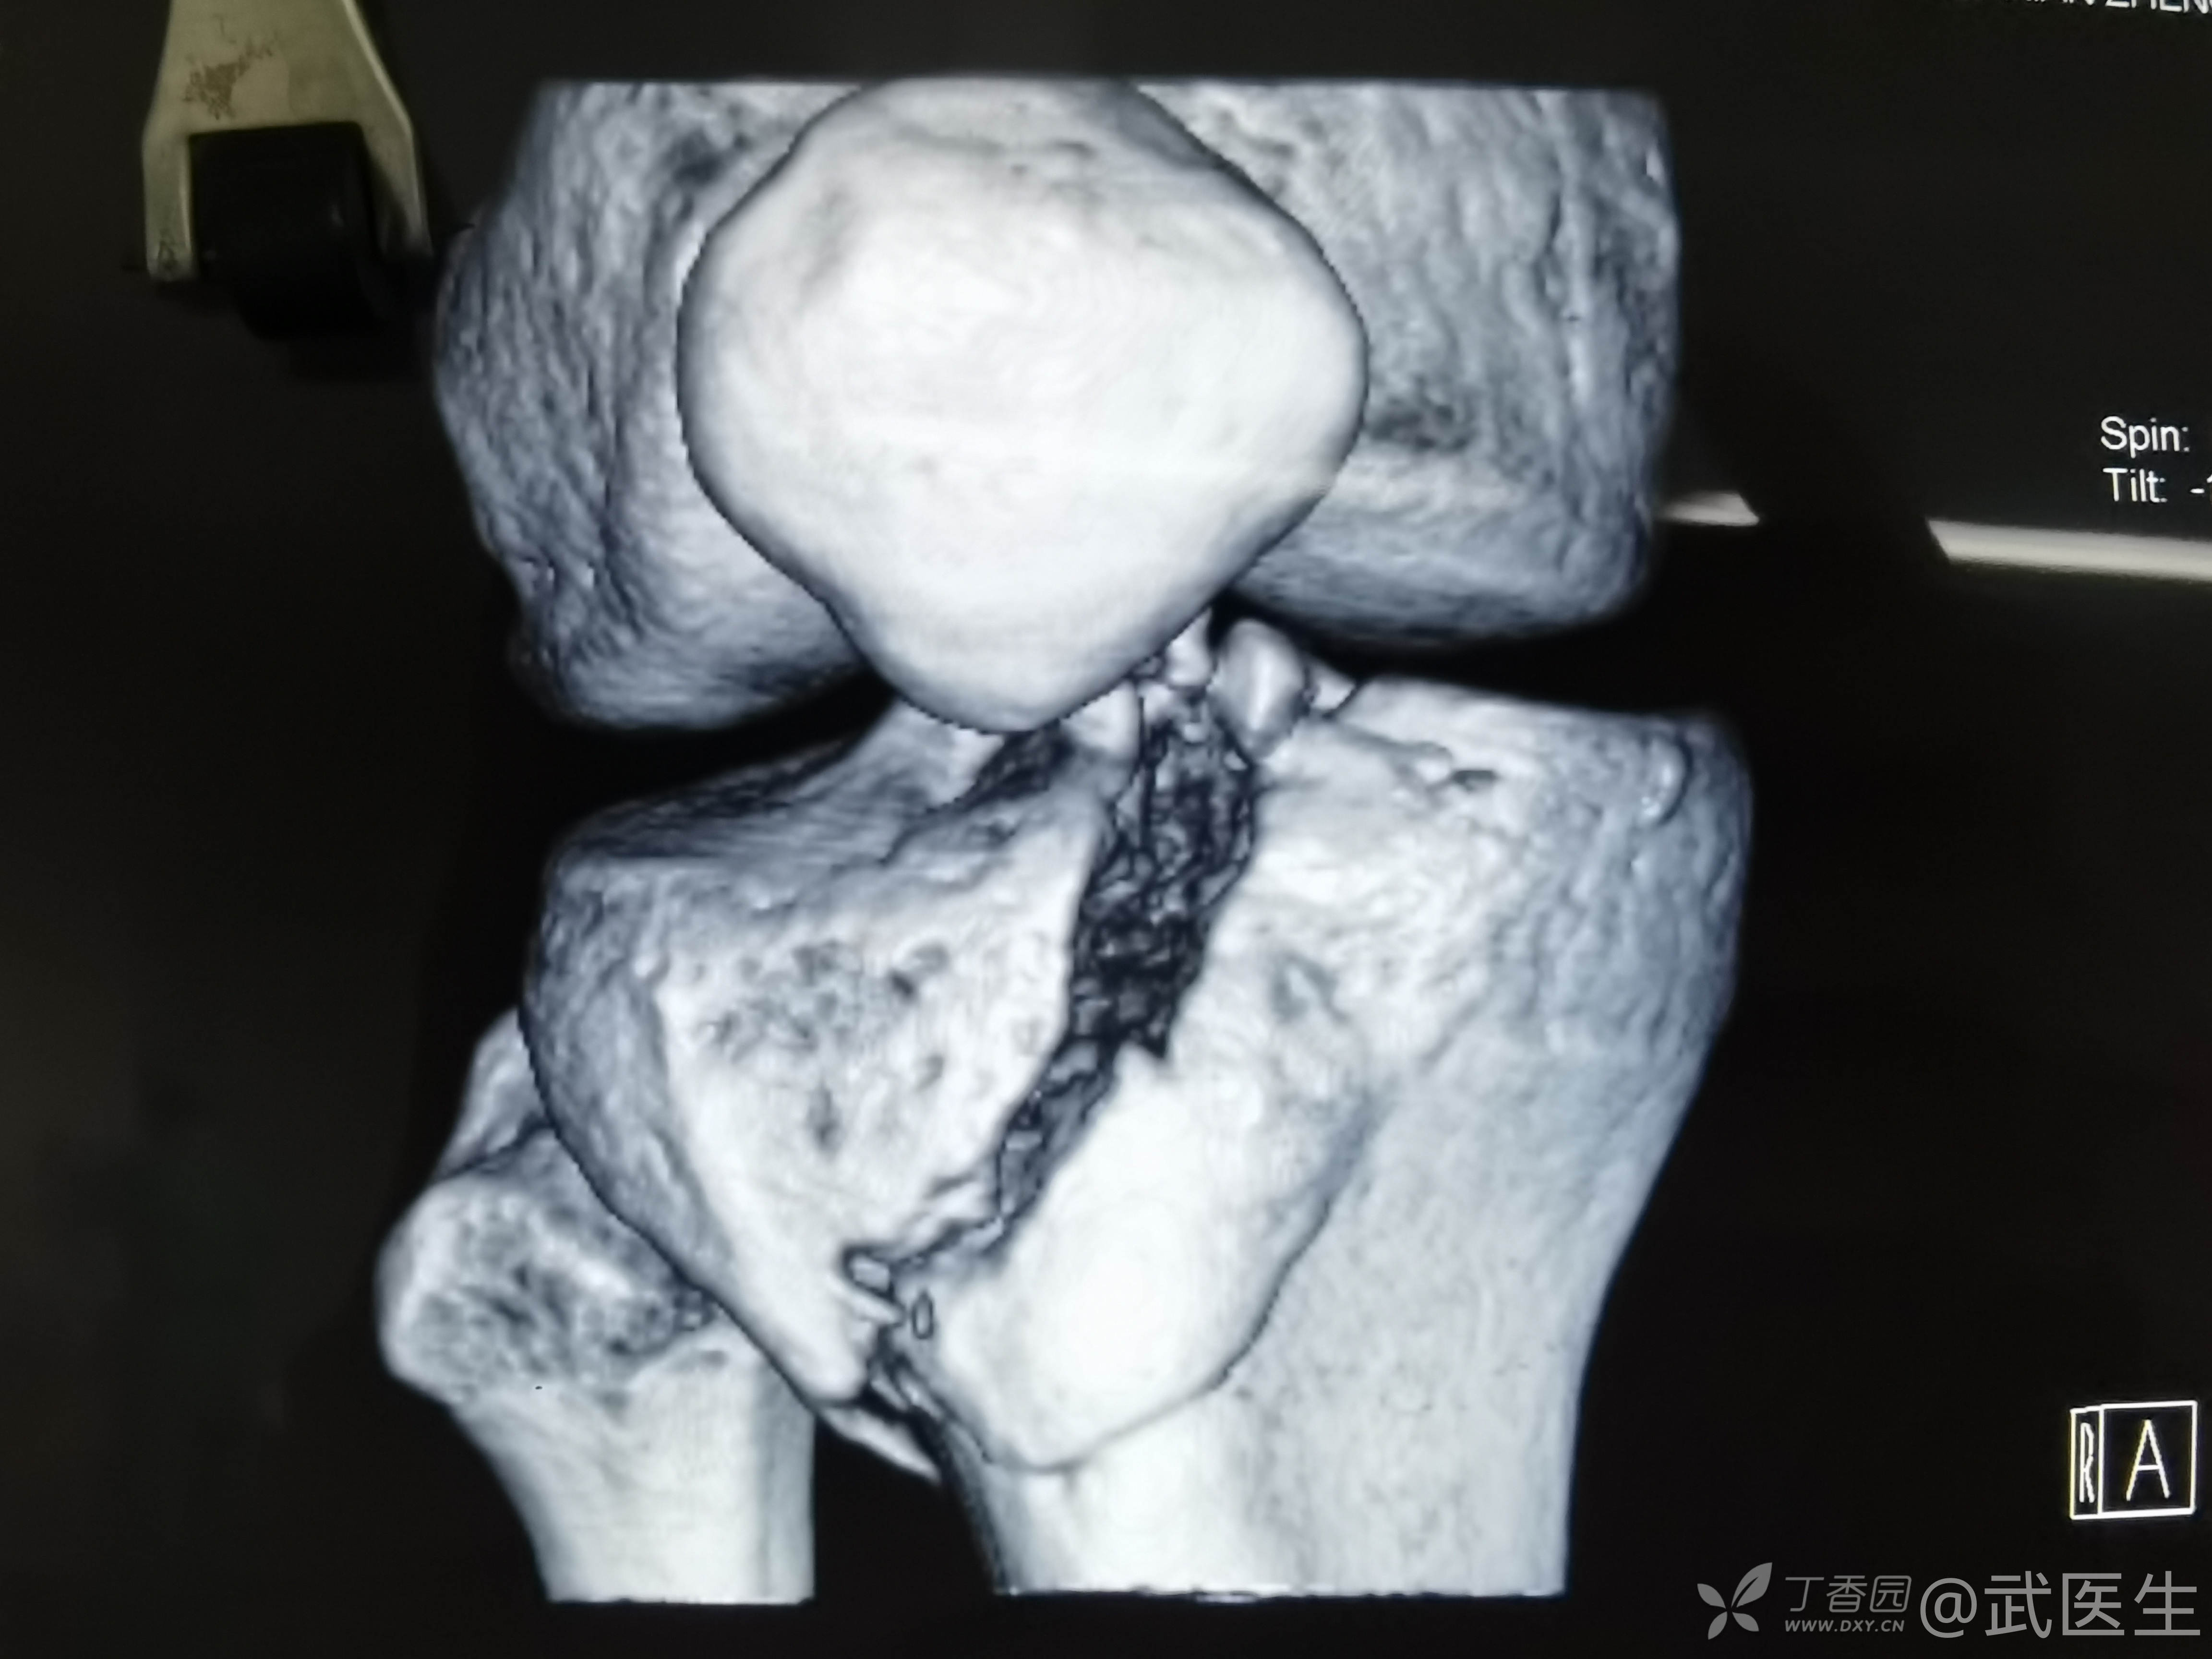

男,15岁,骑摩托车摔伤致右膝疼痛,出血,活动受限三小时就诊,门诊诊断“右胫骨平台骨折,右膝挫裂伤”急诊入院,片子如下,受伤体位照缺失

15岁,骨骺存在,关节加压固定,外侧板支撑